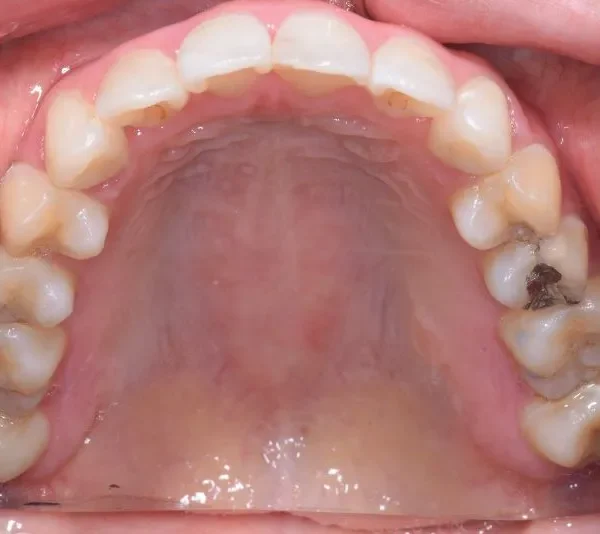

• 治療経過1

治療経過1

再治療の時は、上の歯は前から見えにくいオリジナル固定装置、下の歯はマルチブラケット装置を使用し、治療しました。

治療回数62回、1年6ヶ月の治療期間で矯正治療を終了しました。

前回の治療で歯の根っこの部分の位置を治していたので、全部前から付けるのではなく最低限見える装置で治せました。